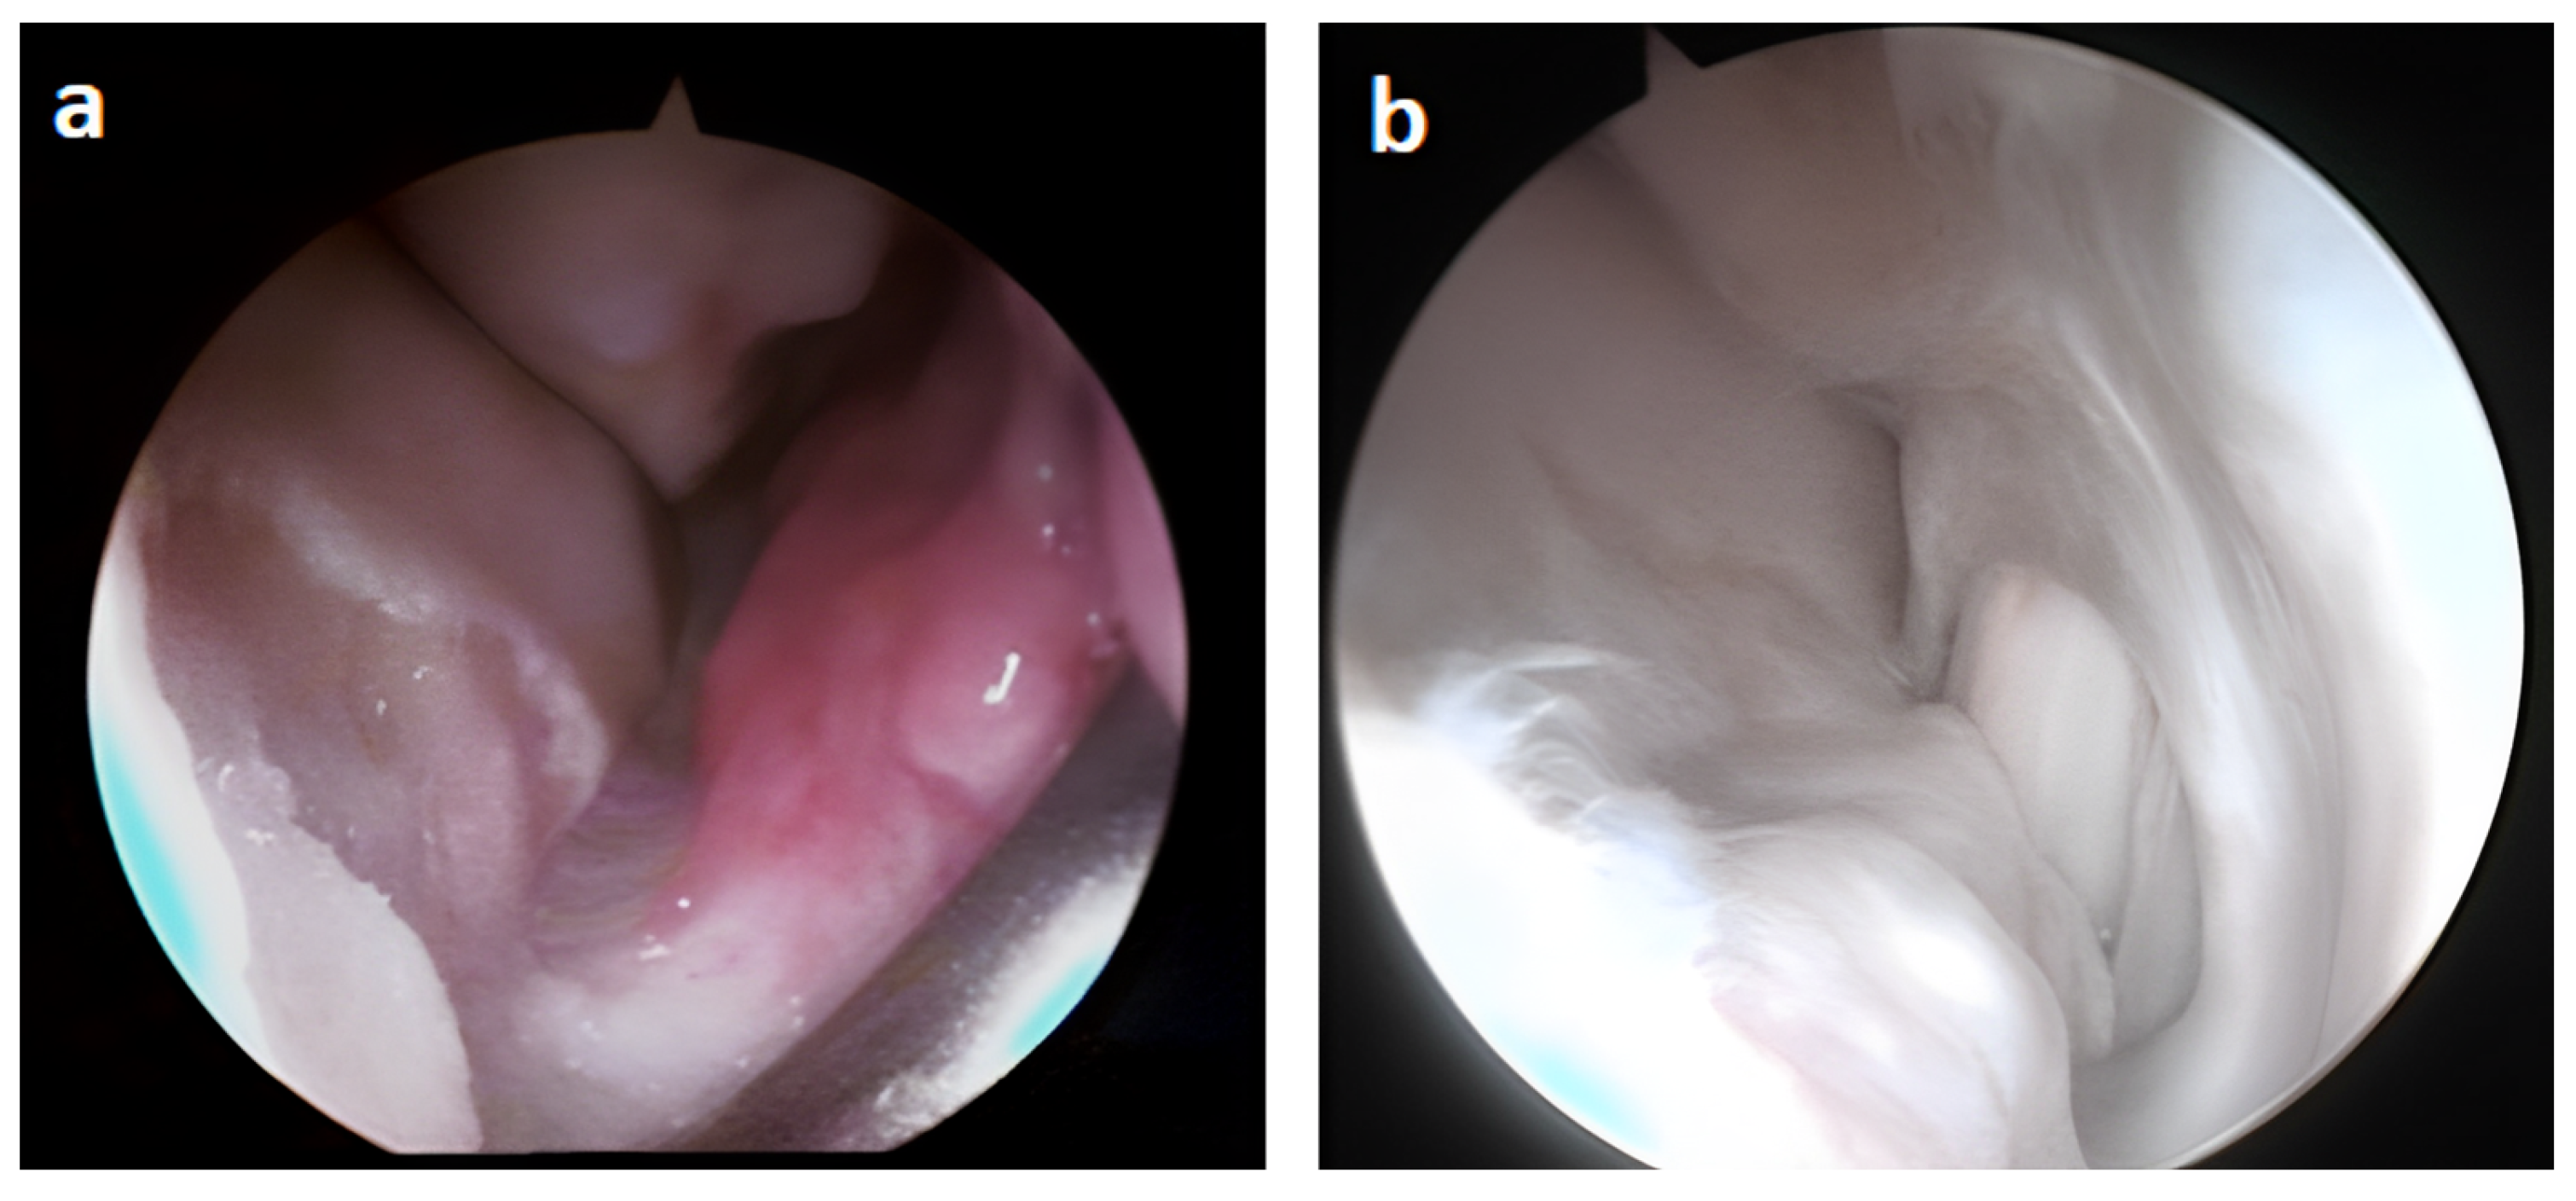

3.2. Arthroscopic Evaluation of the Lesion Site